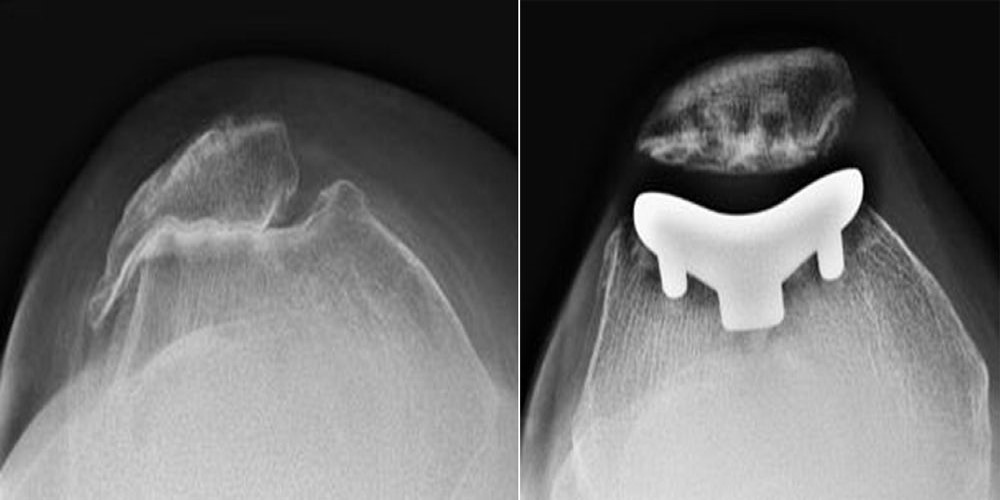

X-rays of arthritic knee and patellofemoral replacement

(Left) X-ray taken from above the knee. The patella and the trochlear groove of the femur have become deformed due to arthritis. There is bone rubbing on bone. (Right) The same knee after patellofemoral replacement. The patellar implant on the underside of the kneecap does not show in an X-ray.